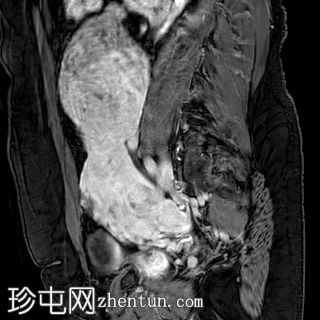

入院时CT检查

CT

1.jpg

腹部中部可见一巨大、不均匀、中心坏死的肿块。

中至大量腹水。

子宫肌瘤。